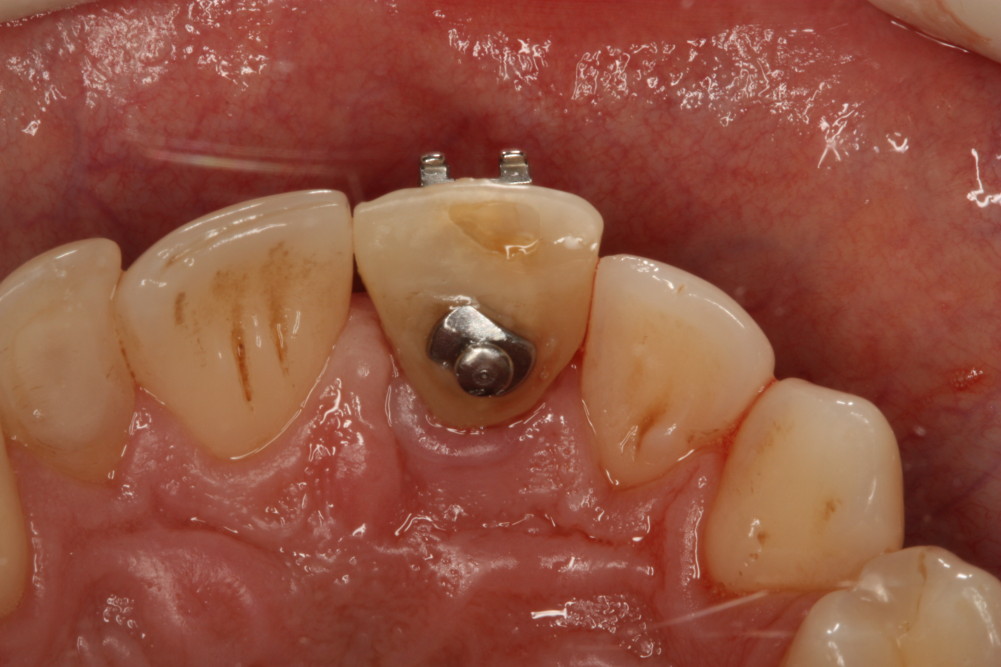

Przykład ekstruzji ortodontycznej za pomocą płytki termoformowalnej i zameczka ortodontycznego: